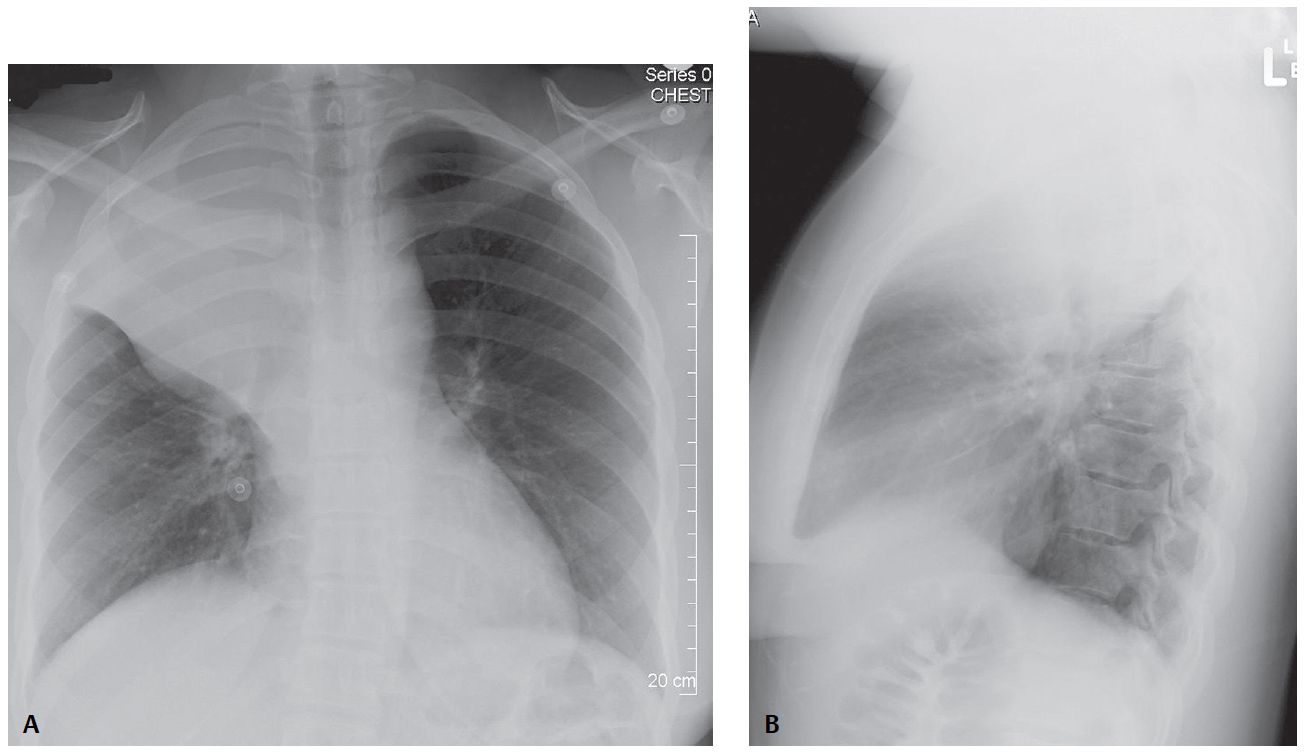

27-year-old Woman with Non-productive Cough and Weight Loss Post category:Spot Diagnosis Post published:March 24, 2023 Share on Facebook Share on X (Twitter) Share on Pinterest Share on Email Share on Reddit 27-year-old Woman with Non-productive Cough and Weight Loss 27-year-old woman complains of non-productive cough and weight loss over the last several months. What’s the Diagnosis ? ANSWER AND X-RAY INTERPRETATION Share on Facebook Share on X (Twitter) Share on Pinterest Share on Email Share on Reddit Read more articles Previous Post38-year-old Female with Painful Patches and Plaques Next PostSmoker with an Ulcer on the Tip of the Finger You Might Also Like Infant with Nonbilious Vomiting and Lack of Stools June 11, 2022 Asymptomatic, Widespread, Erythematous-to-Violaceous Papules and Plaques May 8, 2022 Erythematous and Irregular Linear Streak Extending from the Hand to the Axilla December 21, 2021